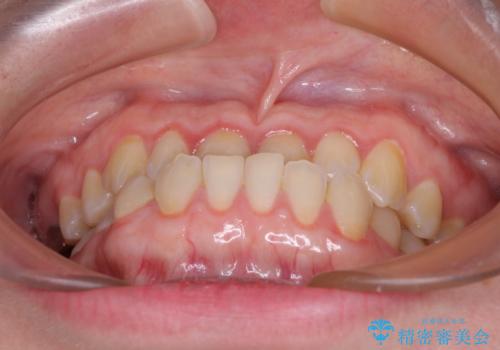

- 前歯の反対咬合を気にして来院された患者様です。

当院にて同様の咬み合わせを治療した方からのご紹介ということもあり、ご紹介者と同じワイヤー矯正で早めに治療を終えることを希望されました。

骨格的に下顎が前方に位置していましたが、歯列矯正で改善できると判断し、ワイヤー装置にて矯正治療を行うこととしました。

このような咬み合わせの方の多くは、舌の突出癖が強い傾向にあり、反対咬合改善後に開咬となってしまい、なかなか治療が終わらないことがあります。

こちらの患者様は、舌のトレーニングを治療開始前から徹底的に実践していただき、僅か8ヶ月という短期間で治療を終えることができました。